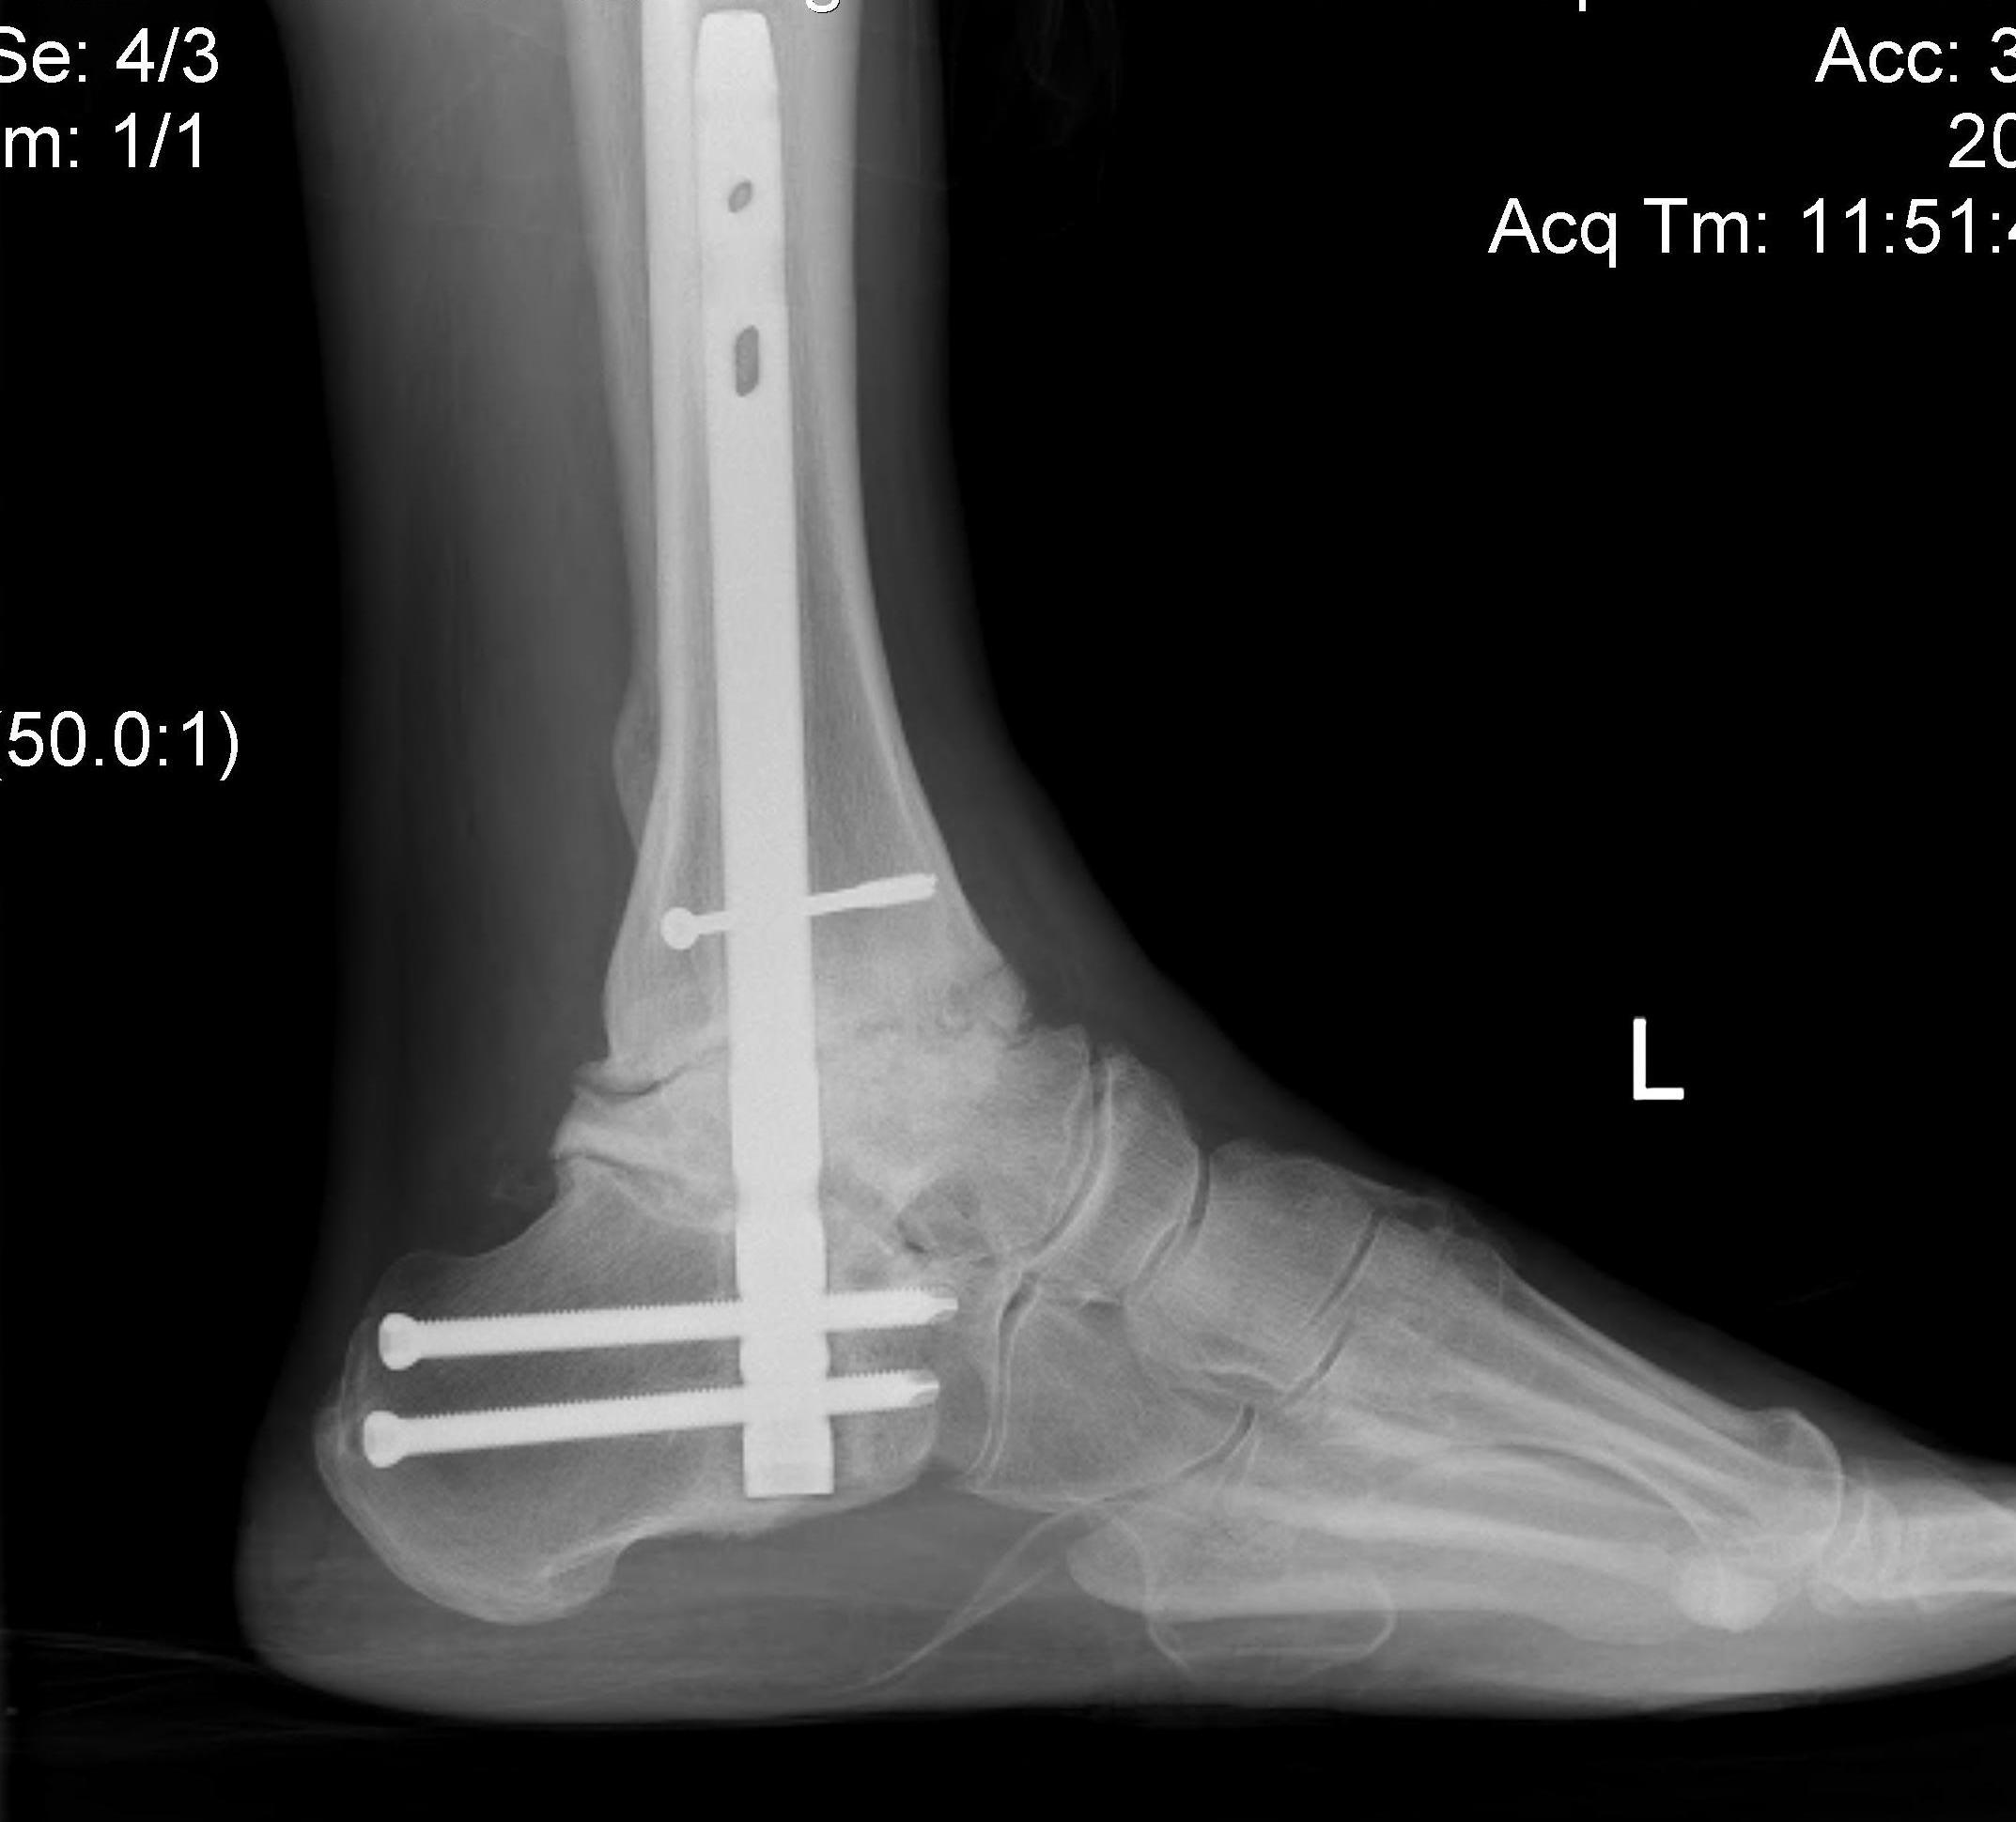

Tibiotalocalcaneal (TTC) / hindfoot nail

Insertion point

- in line with 2nd metatarsal / center of heel pad

- junction of posterior 2/3 and anterior 1/3 heel

- should pass through anterior aspect posterior subtalar joint

- posterior to lateral plantar artery and nerve

Screw fixation

- distal screw fixation in calcaneum +/- talus with jig

- compression

- proximal screws medial to lateral